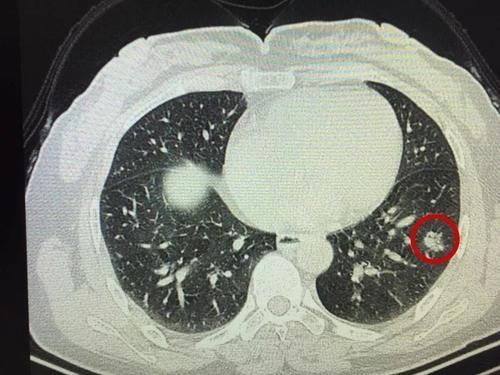

结节癌变的几率没有可参考性,因为这受多种因素的影响,比如结节出现的部位,大小,个人体质,环境因素等等,不过一般来说结节越大癌变的几率也相应增大,举个例子,肺结节如果结节大于3cm的,其癌变的几率超过8成;而在2-3cm之间的结节,癌变几率不到一半;一般人们检查时发现的结节都小于1cm,这算是小结节了,而小结节9成都是良性,所以体检的时候发现结节越大,越要注意,定期检查可少不了。

一般来说,结节大部分为良性,但是,这也并不意味着要置之不理,一旦体检单上出现了“有结节边界不清、毛刺、有丰富血供”的字眼,则八成是出现癌变了。

肺结节是近些年检查出来的患病较多的疾病,而肺癌作为全国恶性肿瘤的“佼佼者”,这两者之间有什么联系呢?数据显示,肺结节中九成以上都是良性的,但是,这也并不意味着可以高枕无忧,尤其是年龄在50岁以上、有长期吸烟史、家族遗传、工作中接触粉尘等致癌物的尤其要当心。

以前检查肺部问题多用X光片,但现在发现,X光片发现肺结节一般都比较大,癌变的几率也大,甚至发现时已经是癌症了,早期诊断意义不大;目前检查肺结节的主要手段是低剂量肺部的CT,这种检查准确率较高,能够发现较小的肺结节,有助于观察预防。